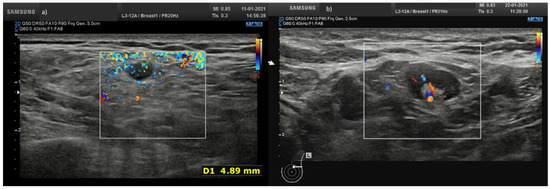

A total of 25 (43.1%) nodes showed eccentric cortical thickening with wide echogenic hilum and oval shape (Figure 1 and Figure 2).

Figure 1.

(a) Hypoechoic lymph node round shape without hilum (arrow) in laterocervical side; (b) axillary lymph node with concentric cortical thickening with reduction in the width of the echogenic hilum and oval shape.

Overall, 19 nodes (32.8%) showed asymmetric eccentric cortical thickening with wide echogenic hilum and oval shape (Figure 3).

Figure 3.

Lymph node (arrow) with asymmetric eccentric concentric cortical thickening in laterocervical side with reduction in the width of the echogenic hilum and oval shape.

A total of 10 nodes (17.2%) showed concentric cortical thickening with reduction in the width of the echogenic hilum and oval shape (Figure 1b).